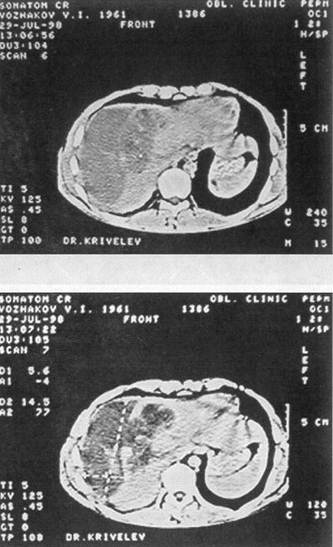

Рис. 8. Компьютерная томография печени больной К., 24 года, через 12 дней после

травмы (описание в тексте)

Рис. 9. Компьютерная томография печени той же больной через 1,5 мес после

живота, а пальпация его стала болезненной Лапароскопия — кровь в брюшной полости. Верхняя срединная лапаротомия с продлением ниже пупка. Аспирировано около 1 л крови. Установлено, что имеется прорыв внутрипечёночной гематомы в области VIII сегмента. Кровотечение остановлено тампонированием тремя марлевыми салфетками, которые были полностью погружены в брюшную полость. Через трое суток предпринята релапаротомия. После удаления салфеток началось паренхиматозное кровотечение из «разбитого» участка печени в проекции VII—VIII сегментов, диаметром 10 см, с отслоенной капсулой. На размозженный участок печени уложена гемостатическая губка и выполнена передняя гепатодиафрагмопексия. Дренировано подпеченочное пространство. В течение недели после операции отмечен вечерний подъем температуры до 38°С. При компьютерной томографии печени, предпринятой через 12 дней после травмы, констатировано, что в VII сегменте имеется массивная, нерезко отграниченная гематома гетерогенной плотности, над которой отслоена глиссонова капсула; вторая гематома лоцируется в IV, VIII сегментах, она относительно четко отграничена, с неровными контурами и большим кровяным сгустком — 69 Н, размером 6,8x6,9 см (рис. 8). Казалось бы, необходимость очередного оперативного вмешательства очевидна, но, учитывая его колоссальный риск, предпочли консервативную тактику и динамическое наблюдение. Проводимая терапия оказалась эффективной. Больная выписана 14.01.02 г. с рекомендацией предохраняться от беременности в течение полутора-двух лет. Повторно обследована 18.02.02 г. Жалоб нет. Состояние удовлетворительное. При контрольной компьютерной томографии печени отмечено более четкое отграничение гематомы в VII сегменте с плотностью сгустка 55—62 Н, уменьшение гематомы в IV, VIII сегментах до 5,6x5,0 см со снижением ее плотности до 45—50 Н (рис. 9). Спустя 4 мес после травмы женщина обратилась за советом, сообщила, что беременна,— срок 8 недель, беременность желанная. Принято решение беременность не прерывать Беременность протекала нормально. По данным ультразвукового исследования печени от 16.12.02 г., т. е. через год после травмы, в проекции определяемых ранее гематом лоцируются неправильной формы гипоэхогенные образования размером 4,8Х4,2 см каждая, жидкостных кистозных полостей не обнаружено — эволюция посттравматических гематом 23.01.03 г. родила девочку, вес 3 кг 900 г, роды физиологические, без осложнений